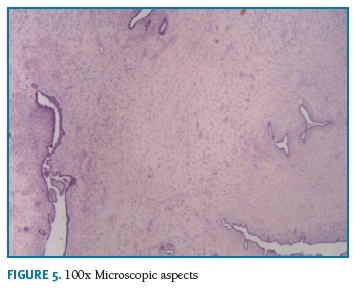

Definitive pathologic diagnosis of Pseudoangiomatous Stromal Hyperplasia (Fig. 4-5-6-7-8) was made on surgical specimen of mastectomy. The patient had regular follow-up at our department. Last visit was in May 2018, and no signs recurrence or contralateral breast cancer were diagnosed in those 11 years of follow-up.